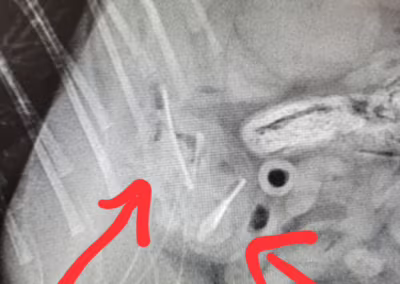

Melania miała przejść wczoraj zabieg sterylizacji jednak okazało się, że kotka od kilku dni źle się czuje. Po badaniu klinicznym i zdjęciach Rtg okazało się, że Malania zjadła coś, czego nie powinna.

Dr. Marta Zielińska przeprowadziła zabieg laparotomii.

Przedmiotem winnym za złe samopoczucie kotki okazała się ozdoba przyklejona do szyby okiennej.